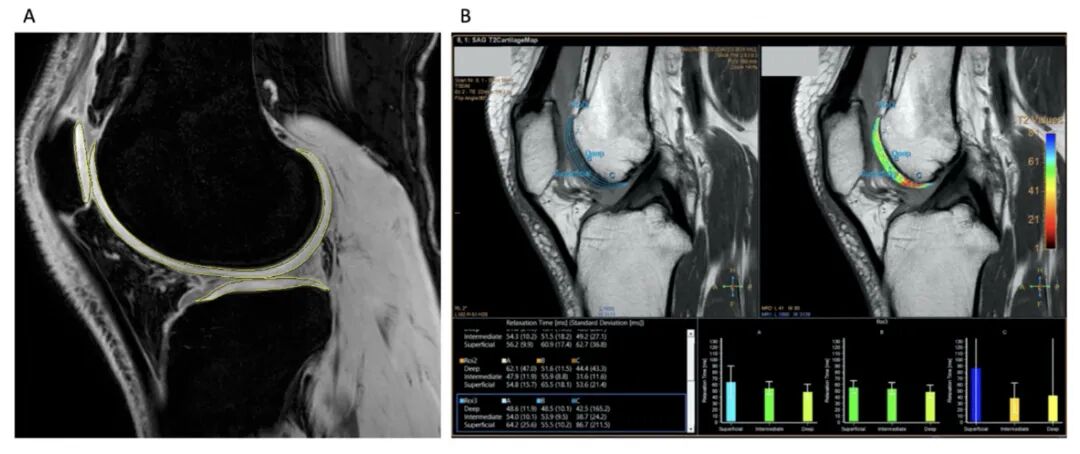

△定量MRI分析软骨变化

更重要的是,这种改善效果是持久的。12个月后,58%的参与者疼痛持续改善。MRI扫描显示,接受间充质干细胞干预的参与者的软骨体积和质量也有所改善。